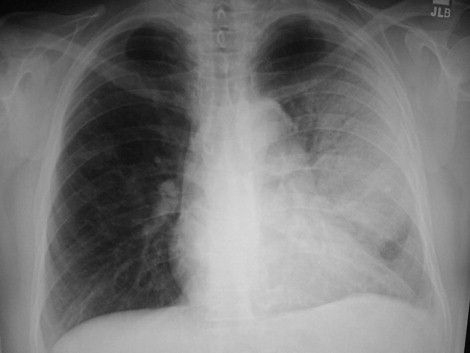

26-aastasel mehel on 2 päeva kestnud kehatemp tõus 38.7 C, köha, hingamisraskused, auskulteerides vasakus kopsus märjad räginad. Röntgenoloogiliselt on näha vasaku kopsu difuusne varjustus (pilt).

Vali kõik õiged vastused selle haiguse kohta (1 või mitu).